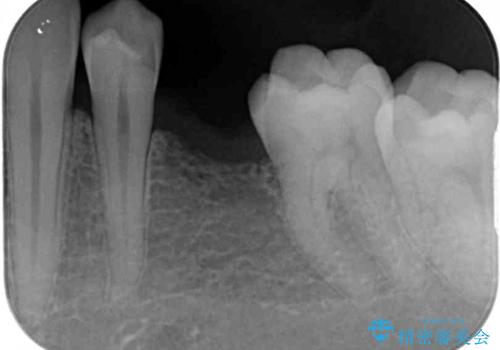

- 奥歯の銀歯が頻繁に外れるとのことで来院された患者様です。

欠損部分をインレーによるブリッジで治療してありましたが、外れやすく虫歯リスクが高いため、オールセラミックブリッジにて補綴することとしました。